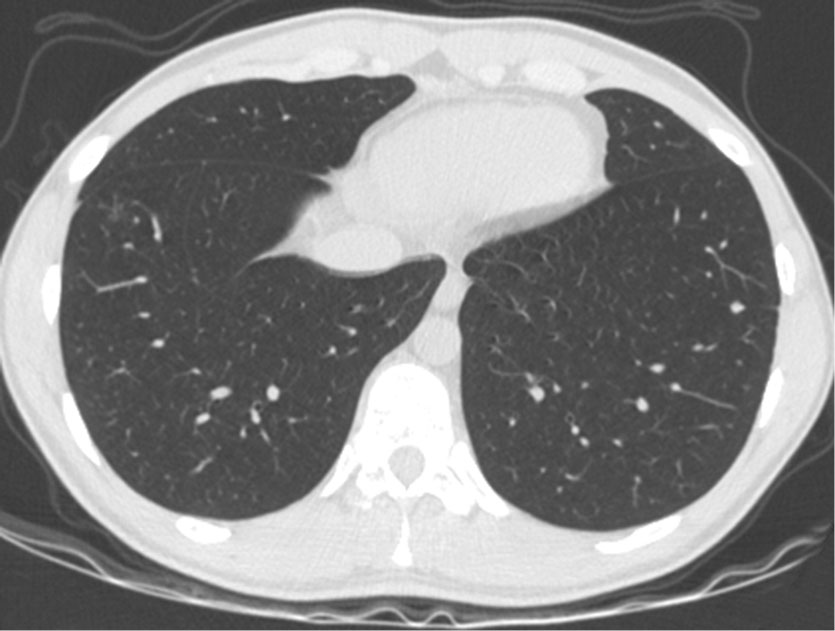

Рентгенологически очаговые и инфильтративные изменения легочной паренхимы разрешились, данных о наличии жидкости в плевральных полостях и полости перикарда не получено (рис. 7).

Рис. 7. КТ от 15.11.2021. Разрешение признаков альвеолярной инфильтрации легочной паренхимы

Fig. 7. CT from 11.15.2021. Resolution of signs of alveolar infiltration of the pulmonary parenchyma